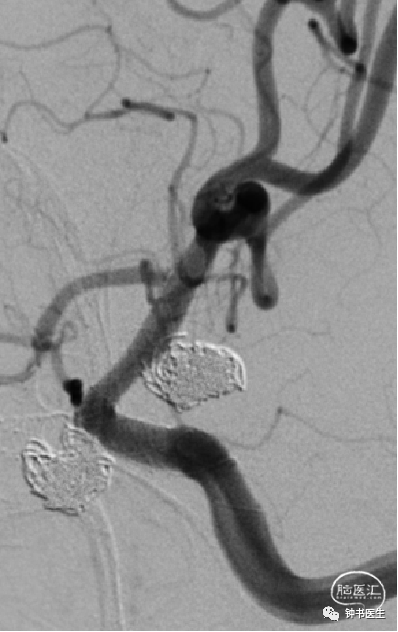

2021-06-22 DSA

R-ICA